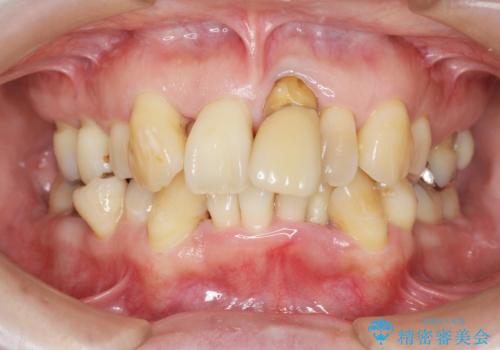

[メタルフリー] 虫歯・銀歯だらけの口腔内を全顎治療

![[メタルフリー] 虫歯・銀歯だらけの口腔内を全顎治療の症例 治療前](https://seimitsushinbi.jp/wp/wp-content/uploads/2025/03/e26a9887bc6905a2f0f51f5772b5ac9c-500x350.jpg?v=1741918285)